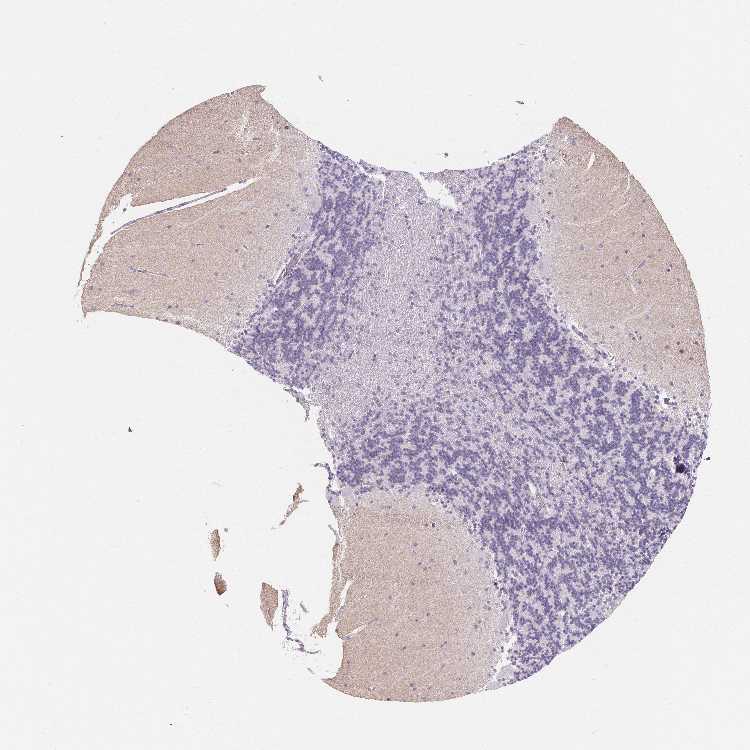

CEREBELLUM - Antibody stainingi

Antibody staining in the annotated cell types in the current human tissue is reported as not detected, low, medium, or high, based on conventional immunohistochemistry profiling in selected tissues. This score is based on the combination of the staining intensity and fraction of stained cells.

Each image is clickable and will lead to virtual microscopy that enables deeper exploration of all samples and also displays staining intensity scores, fraction scores and subcellular localization as well as patient and tissue information for each sample.

Antibody HPA051368Antibody HPA061671

Molecular layer - neuropil -Medium

Synaptic glomeruli - core -High